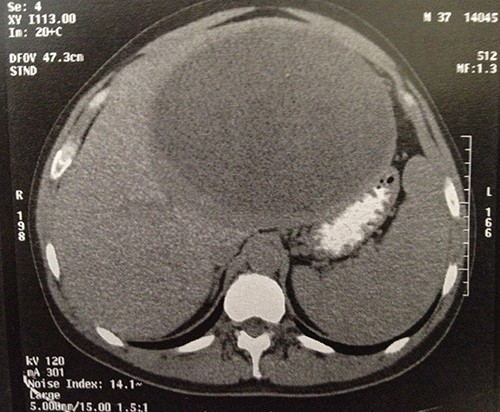

The computed tomography (CT) scan revealed a semi-solid mass in the left liver lobe, measuring 22 × 21 × 16 cm with peripheral enhancement after contrast administration (Fig. 1). An upper and lower endoscopy revealed no other lesions of the gastrointestinal tract. Tumor markers, such as a-phetoprotein (AFP) and carcinoembryonic antigen (CEA) were within the normal limits.

Computer tomography image showing a 23 × 22 × 16-cm lesion arising from the left lobe of the liver.